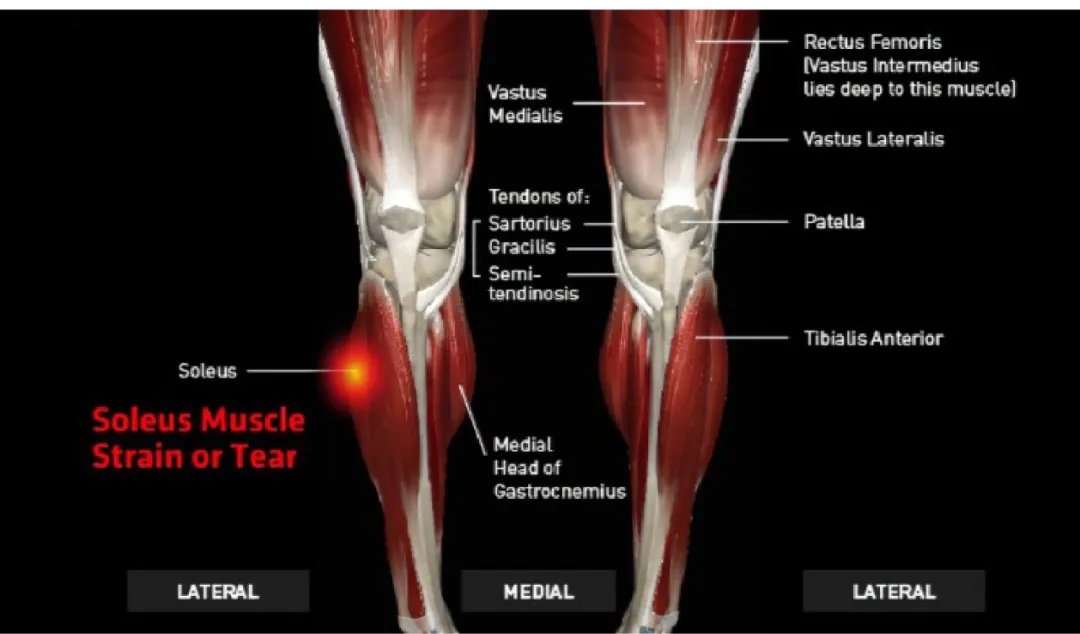

2. 比目鱼肌拉伤

比目鱼肌在将脚后跟抬离地面方面起着重要作用。它还可以在走路或跑步时稳定您的姿势,防止向前跌倒。

如果患有比目鱼肌拉伤,当做以下动作时,可能会感到深度酸痛或紧绷:

按压跟腱

踮起脚尖走路

将脚趾拉向小腿

比目鱼肌拉伤是耐力跑中常见的过度使用性损伤。然而,许多跑步者并没有注意到导致它的任何特定事件。

症状往往会随着时间的推移而发展,包括:

小腿肌肉疲劳(开始时)

肿胀

瘀伤

剧烈疼痛。

这些症状可能会恶化,直到完全难以运行。

小腿拉伤的愈合时间取决于受伤的肌肉,以及受伤的类型和严重程度。许多小腿拉伤会在几周内自行愈合,但其他的可能需要治疗和更长的恢复期。